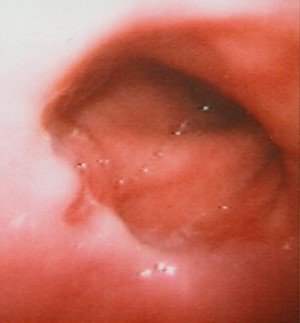

- Endoskopiya - divertikulun perforasiyası təhlükəsinə görə çox ehtiyatla aparılmalıdır.

Endoskopik stapler

|

Divertikul ilə QB arasındakı arakəsmə endoskopik staplerlə kəsilir və tikilir. 3-6 sm ölçülü divertikullarda icra edilir.

- Endoskopiya - divertikulun perforasiyası təhlükəsinə görə çox ehtiyatla aparılmalıdır. QB-nun xəstəliklərinin və paraezofageal yırtıqların diferensiasiyası üçün mühümdür.